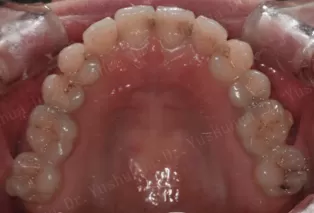

Photos intra-orales